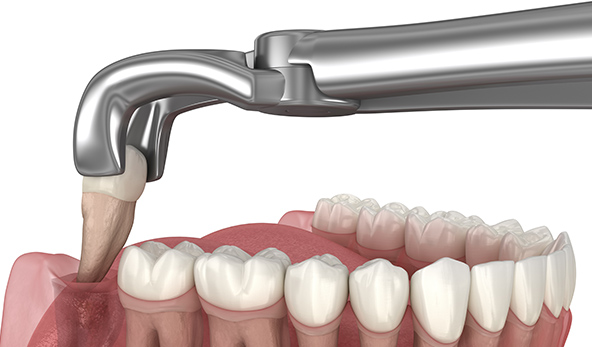

고난도의 매복된 사랑니 발치

사랑니가 매복되어 있거나 턱뼈 안쪽에 깊숙이 위치한 경우,

고난도의 시술이 필요할 수 있습니다. 매복된 사랑니나 복잡한

사랑니 위치에도 안전하고 정확한 수술을 제공하여

환자들의 안전을 최우선으로 합니다.

사랑니가 매복되어 있거나 턱뼈 안쪽에 깊숙이

위치한 경우,고난도의 시술이 필요할 수 있습니다.

매복된 사랑니나 복잡한 사랑니 위치에도 안전하고

정확한 수술을 제공하여 환자들의 안전을

최우선으로 합니다.